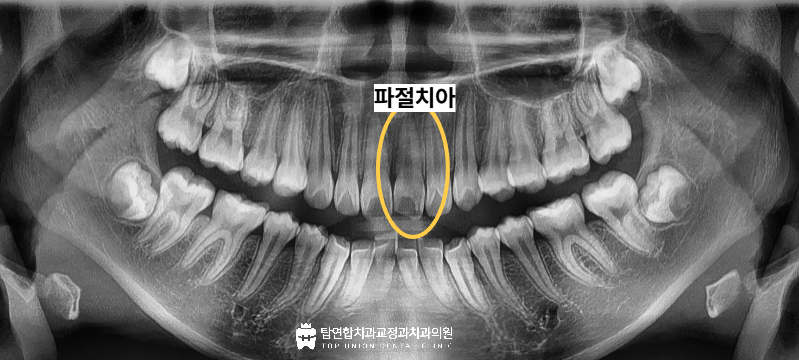

이번에 마산합포구치과 탑연합치과교정과를

내원하신 분은

10대의 어린 여학생의 환자분이셨습니다.

학교에서 사고로 넘어지면서

앞니가 깨졌고,

가장 먼저 육안으로 보이는 파절 부위뿐만 아니라

치아 내부의 건강 상태를 정확하게

파악하기 위한 세밀한 진단을 진행하였습니다.

다행히 환자분께서는 치아가 깨진 이후

별다른 통증이나 시린 증상 등의

이상 증상을 보이지 않으셨습니다.

이는 신경 조직의 직접적인 노출이나

심각한 손상까지는 이어지지 않았음을 의미하며

따라서 신경 치료와 같은 복잡한 과정보다는

치아 본연의 외형을 복원하는

치료에 집중하기로 결정하였습니다.